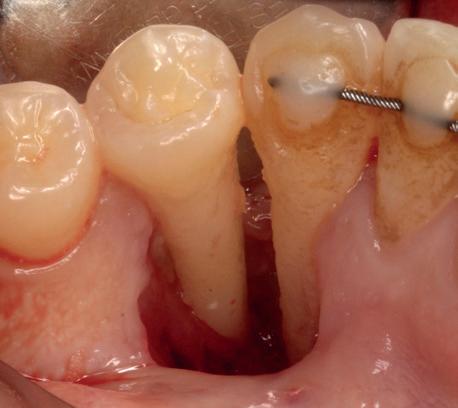

heeft de nadrukkelijke wens om geen brugconstructie te krijgen. Om die reden is een etsbrug of een conventionele brug geen optie. Daarom bestaat het behandelvoorstel uit vier losse kronen waarvan de 22 implantaat gedragen zal zijn. Een gedetailleerd onderzoek van de regio 22 is noodzakelijk (foto 4-6).

Uit het röntgenonderzoek blijkt dat op de locatie van de 22 veel bot verloren is gegaan en dat er niet direct een implantaat geplaatst kan worden. Om die reden is een botaugmentatie geïndiceerd. Wel zijn distaal van de 21 en mesiaal van de 23 de botpieken aanwezig die de papillen ondersteunen. Naast te weinig bot, is op de locatie 22 in bucco-linguale richting ook te weinig volume gingiva aanwezig. Daarom zal er tevens een soft tissue graft aangebracht worden. Tijdens deze behandeling wordt ook de recessie op de 23 zoveel mogelijk bedekt (foto 7 en 8).

Het botdefect wordt geaugmenteerd met een allograft (Biohorizons MinerOss A). Om dit volume te stabiliseren, wordt een titanium versterkt membraan aangebracht (Cytoplast ti-reinforced d-PTFE membraan) met daaroverheen een collageen membraan (Mem-Lok collagen matrix). Na sluiting van de flap wordt de 4-delige PMMA brug, die al is gefreesd in het laboratorium naar aanleiding van de planning, gerelined en geplaatst met een tijdelijk cement (foto 9-14).

Na vier maanden wordt er een CBCT gemaakt om het botvolume te kunnen beoordelen en een digitale planning te kunnen maken voor het plaatsen van het implantaat. Tevens wordt de stabiliteit van de botpieken op het buurelementen bekeken (foto 15 en 16).

Tijdens het verwijderen van het membraan is het botvolume klinisch waarneembaar en blijkt dat er voldoende bot is om het implantaat te kunnen plaat-

sen. Tijdens deze procedure wordt er ook een free gingival graft van het palatum gehaald. Deze wordt buccaal aangebracht van de 22 en 23 om zo de recessie zoveel mogelijk te bedekken en de papil tussen de 22 en 23 van meer volume te voorzien.